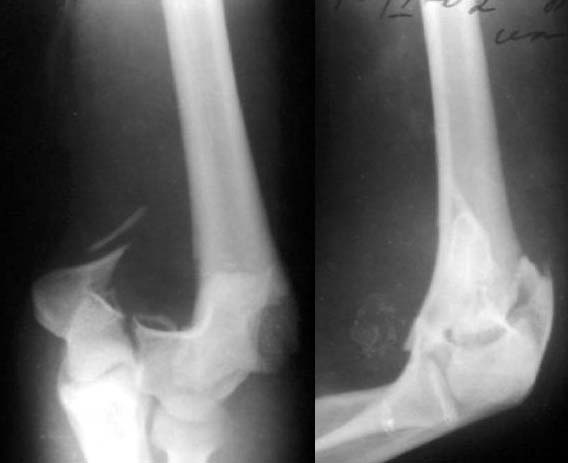

Все же открываться мы не стали. Результаты в приложении. Фронтальный снимок переделаю и пришлю еще раз. Мнения?

Кликните для загрузки файла k5.jpg

9KB (9874 bytes)